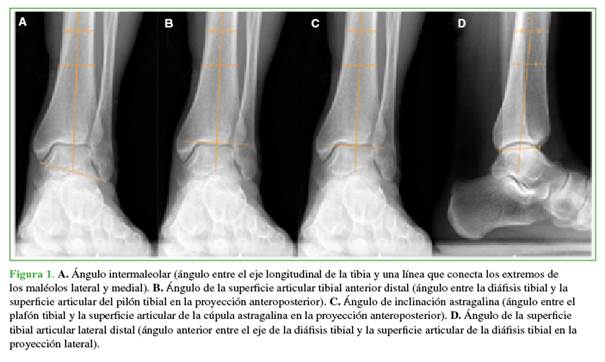

Se tomaron radiografías de tobillo de frente y de perfil, con carga, antes de la cirugía y al final del seguimiento. En la proyección anteroposterior, se evaluaron los siguientes ángulos: ángulo intermaleolar (IM) (ángulo entre el eje longitudinal de la tibia y una línea que conecta los extremos de los maléolos lateral y medial),15 ángulo de la superficie articular tibial anterior (STA) distal (ángulo entre la diáfisis tibial y la superficie articular del pilón tibial en la proyección anteroposterior),16 ángulo de inclinación astragalina (IA) (ángulo entre el plafón tibial y la superficie articular de la cúpula astragalina en la proyección anteroposterior).16 En la radiografía de perfil, se evaluó el ángulo de la superficie tibial articular lateral (STL) distal (ángulo anterior entre el eje de la diáfisis tibial y la superficie articular de la diáfisis tibial en la proyección lateral).17 Estos ángulos se utilizan tanto para la planificación preoperatoria como en el posoperatorio para evaluar el resultado quirúrgico radiográfico (Figura 1).